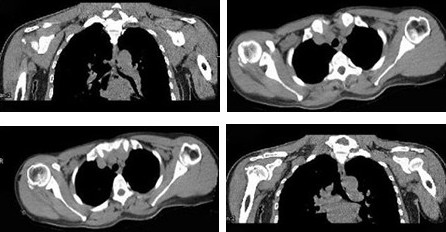

女,47岁,右肩部疼痛并肩关节活动受限数月,请结合所提供的图像,选择最佳选项

A:颈椎病

B:颈部肿瘤

C:化脓性肩关节炎

D:未见明显异常

E:肩周炎